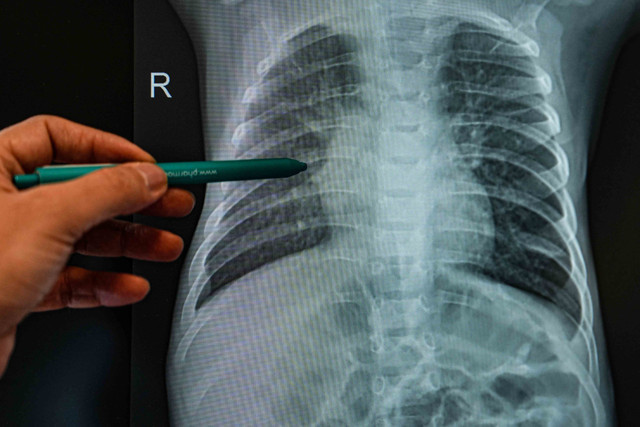

Alerjik çocukların, özellikle astım ve alerjik rinit gibi rahatsızlıkları olanların enfeksiyonlara daha kolay yakalandığını belirten Doç. Dr. Serdar Al, “Alerji ve enfeksiyonlar birbirini tetikleyen durumlardır. Alerjik çocuklarda bağışıklık sistemi belirli proteinler üretir ve bu proteinler enfeksiyon sırasında aşırı salgılanarak alerjik semptomları artırır. Enfeksiyonlar, burun akıntısı, öksürük ve diğer alerjik şikayetleri daha da kötüleştirebilir. Alerjik bireyler, enfeksiyonlara karşı daha hassastır. Bir ortamda virüs taşıyan bir kişi 10 kez hapşırdığında normal bir birey enfekte olabilirken, alerjik bir birey tek bir hapşırıkla hastalanabilir” dedi.

Özellikle 2 yaş altı çocukların enfeksiyonlardan korunmasının büyük önem taşıdığını vurgulayan Doç. Dr. Serdar Al, “Kış aylarında enfeksiyonlar daha fazla görülüyor. Çocukların okullarda, kreşlerde ve toplu taşıma araçlarında daha fazla zaman geçirmesi bulaş riskini artırıyor. Kapalı ortamlardan mümkün olduğunca uzak durmak, hijyen kurallarına dikkat etmek ve bağışıklık sistemini güçlendirecek önlemler almak önemli. Ayrıca RSV, rinovirüs, influenza, COVID gibi viral enfeksiyonlar (gibi) alerjik hastalıkların gelişimini kolaylaştırabilir” diye konuştu.